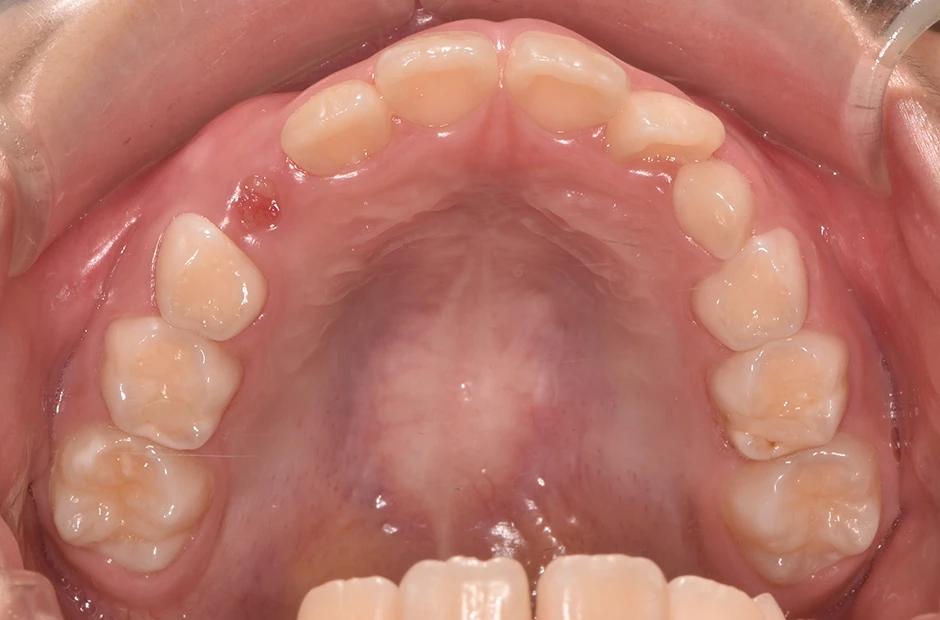

反対咬合

| 診断名・主訴 | 前歯反対咬合 |

|---|---|

| 年齢・性別 | 12歳・男性 |

| 治療期間・回数 | 1年半 18回 |

| 治療に用いた主な装置 | リンガルアーチ(前方誘導弾線) |

| 抜歯部位 | なし |

| 治療費 | 35万円(税抜) |

| リスク・副作用 | 装置による違和感・疼痛・歯肉退縮・歯根吸収・虫歯のリスクなど |

治療前